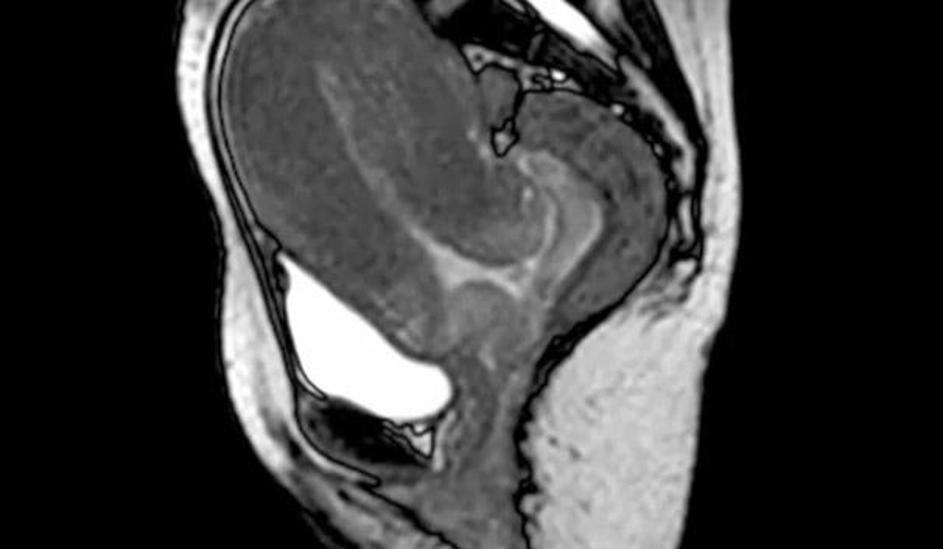

porod, snemanje, magnetna resonanca Poporodni pogled v notranjost maternice s placento. Žurnal24 porod, snemanje, magnetna resonanca